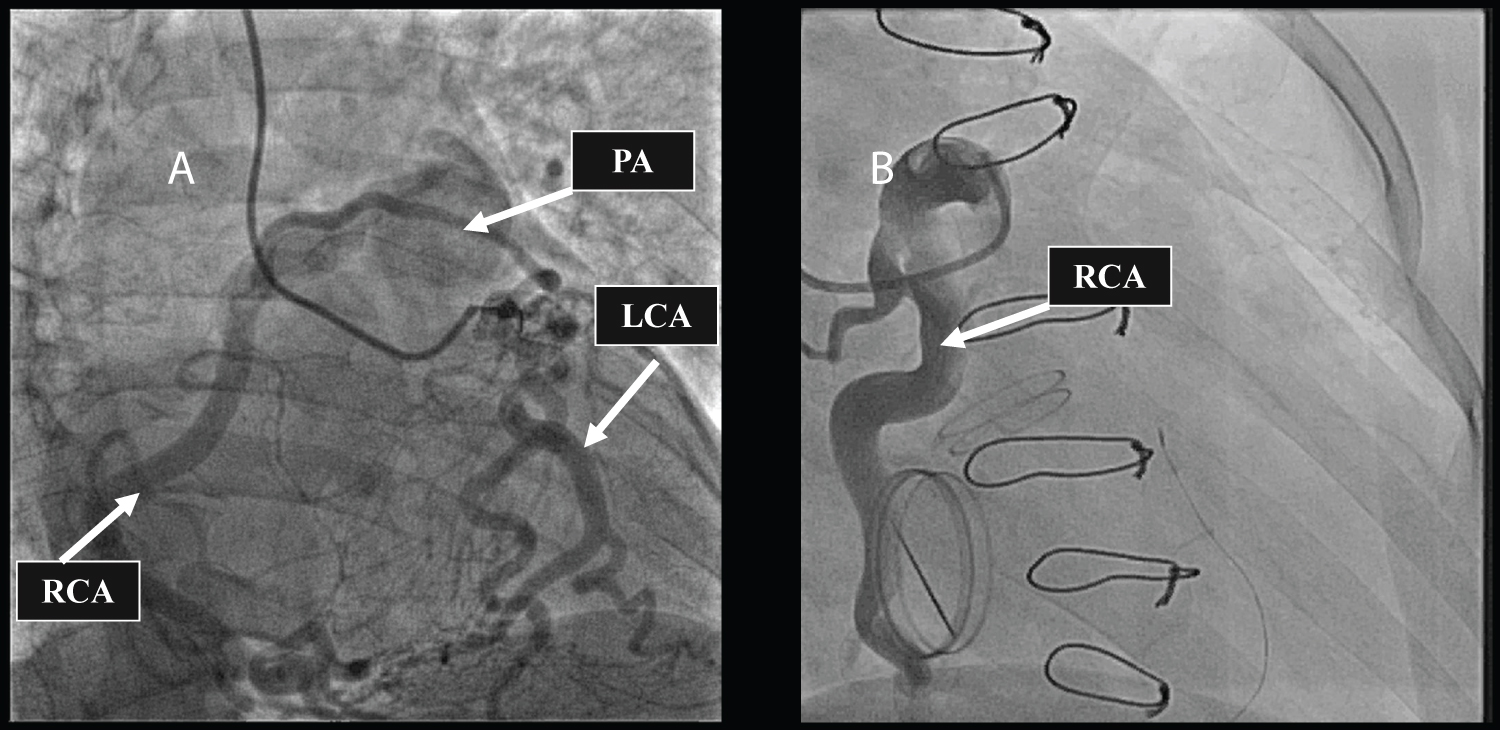

Transthoracic echocardiography was performed, which revealed rheumatic heart disease with multivalve involvement, including moderate mitral stenosis, moderate mitral insufficiency, and moderate aortic stenosis. Additionally, the image suggested an abnormal origin of the RCA. To ascertain the exact diagnosis and determine the condition of the coronary artery, coronary angiography was then performed. Angiography revealed collateral blood flow from the left coronary artery (LCA) to the RCA and delayed retrograde filling of the RCA via the collateral vessels back to the ostium into the pulmonary artery (PA) (Figure 1A). Electrocardiography and chest radiography were normal. Based on these findings, a diagnosis of ARCAPA was confirmed (Video 1 and Video 2).

Figure 1: A) Preoperative coronary angiography showed the anomalous origin of the right coronary artery arising from the pulmonary artery and collateralization between the left coronary artery and the right coronary artery; B) Postoperative coronary angiography showed the anomalous origin of the right coronary artery arising from the pulmonary artery. View Figure 1

A follow-up echocardiogram revealed that the mechanical valves worked efficiently (Figure 2), and coronary angiography demonstrated normal blood flow in the RCA and LCA (Figure 1B). After an uneventful postoperative course, the patient was discharged on the 16 th day of admission and remained asymptomatic during the follow-up period of 10 years.